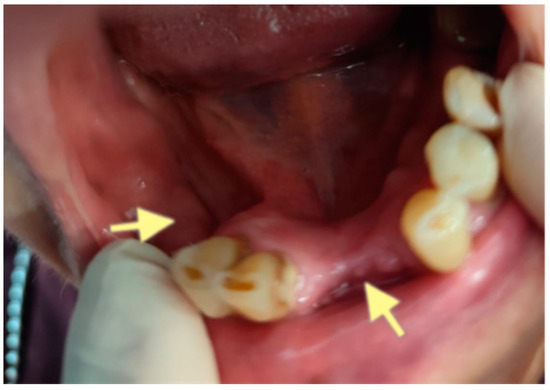

Figure 10.

CT of the head and facial bones (19 March 2025) before the last operation (sequestrectomy of the lower and upper jaws; antrotomy performed).

The third patient was a 75-year-old female with osteonecrosis of the mandible and maxilla in the fourth and in the second quadrant (see Figure 7, Figure 8 and Figure 9). The patient had third-stage jaw osteonecrosis. In 2023, the patient was diagnosed with osteonecrosis of the upper and lower jaw caused by antiresorptive therapy (until August 2021, the patient regularly used Zolendronic acid; then, this drug was replaced by the RANKL inhibitor Denosumab). The treatment was periodically complicated by submandibular and submental abscesses. In addition, due to the progression of the underlying disease, constant courses in chemotherapy were administered. The patient underwent three operations, which included sequestrectomy of the jaw with simultaneous use of A-PRF, antrotomy with revision of the maxillary sinus, closure of the oroantral communication, and opening and revision of abscesses of the soft tissues (see Figure 10 and Figure 11)

The photos show the patient 2 months after the last operation (sequestrectomy of the lower and upper jaws; antrotomy and A-PRF application). The healing of the surgical wounds is incomplete, but there is a positive tendency towards healing.

Despite such an unfavorable disease course, it was possible to achieve an improvement in the patient’s condition. Her pain in the upper and lower jaw has significantly decreased, and the regular bleeding from inflamed gums has stopped.